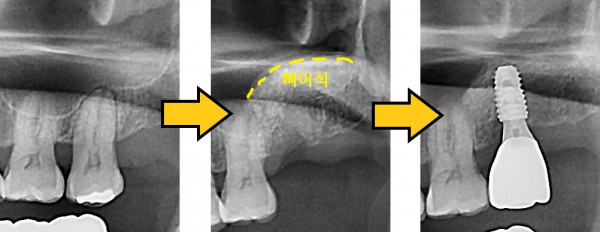

임플란트 뼈이식 + 임플란트